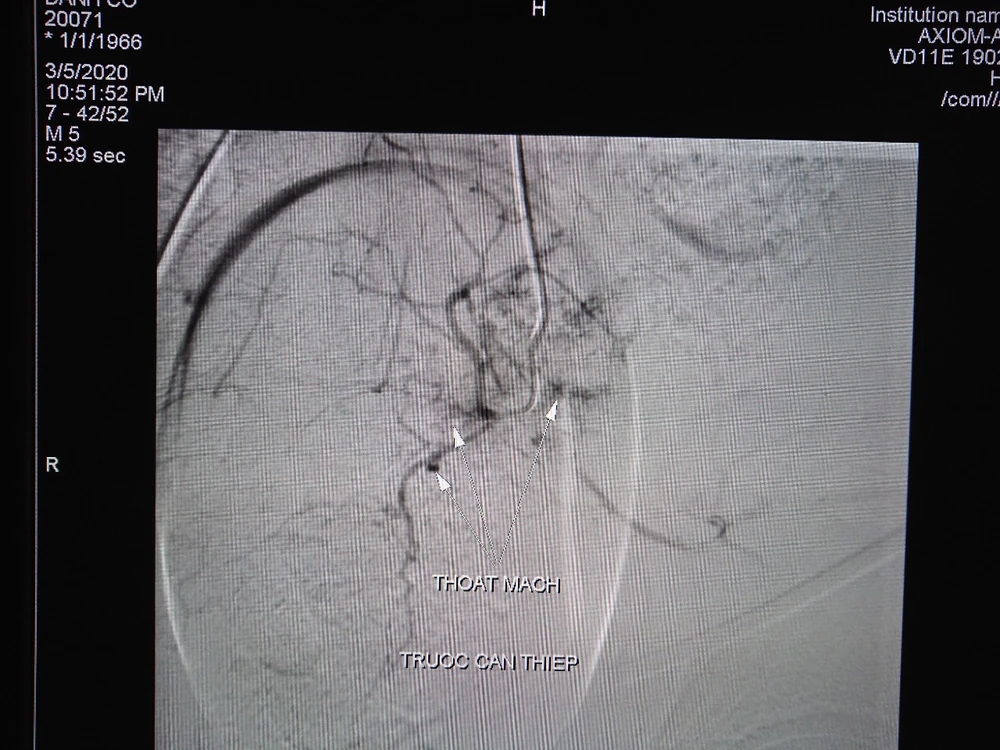

Hình ảnh trước và sau can thiệp nút mạch 1 Hình ảnh trước và sau can thiệp nút mạch 2

Hình ảnh trước và sau can thiệp nút mạch.

Êkíp can thiệp mạch do BS CK1 Trần Công Khánh - Phó Trưởng khoa Chẩn đoán hình ảnh đã tiến hành chụp và phát hiện nhiều ổ thoát mạch xuất phát từ động mạch bàng quang. Êkíp luồn chọn lọc vào động mạch bàng quang, chụp xác định vị trí và bơm tắc bằng Spongel. Chụp ảnh kiểm tra sau bơm tắc không thấy tắc mạch.